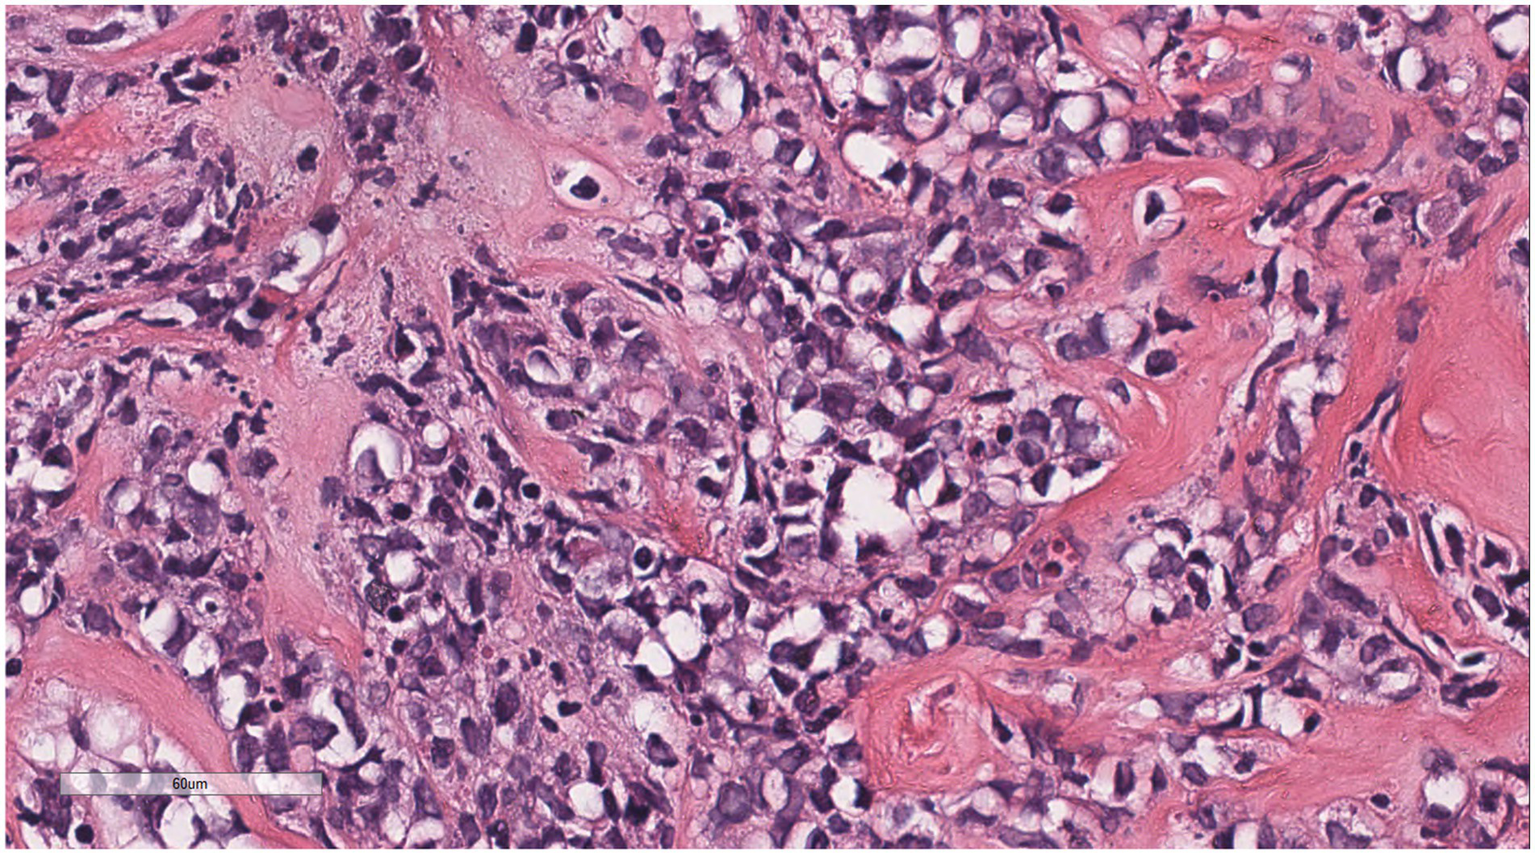

Microscopically (Figures 2–8), the breast biopsy tissue revealed diffuse proliferation of lymphocyte-like cells arranged in cords or nests, which infiltrated the breast stroma and surrounding fat. At medium magnification, patches of mononuclear cells with loose arrangements and uniform dispersion were observed. Some of these cells were arranged in a linear or nonpiled pattern, with slender fibrous septa visible. The cells were medium to large, with indistinct nucleoli, primitive to folded nuclei, fine chromatin, scattered eosinophils, and mitotic figures. Some of the cells were medulloblastoid, with scant cytoplasm, round nuclei, and small nucleoli. Some of the cells were myelomonocytic or monocytoid, with local fibrous tissue proliferation.

Figure 5

Infiltrative growth of tumor cells into fat.

Figure 6

Diffusely proliferating myeloid cells, some arranged in a linear, private pattern, with slender fibrous septa.